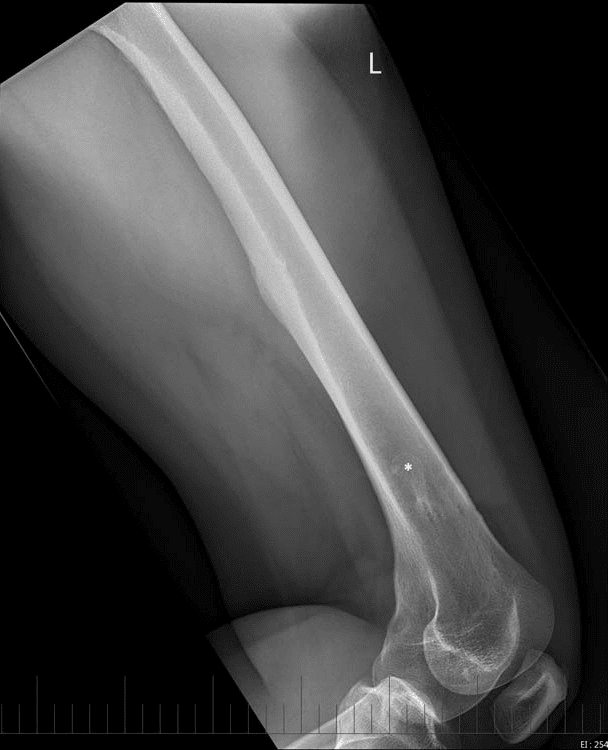

U dạng xương

» Thông tin: Nữ giới – 23 tuổi.

» Lâm sàng: Đau xương đùi 6 tháng.